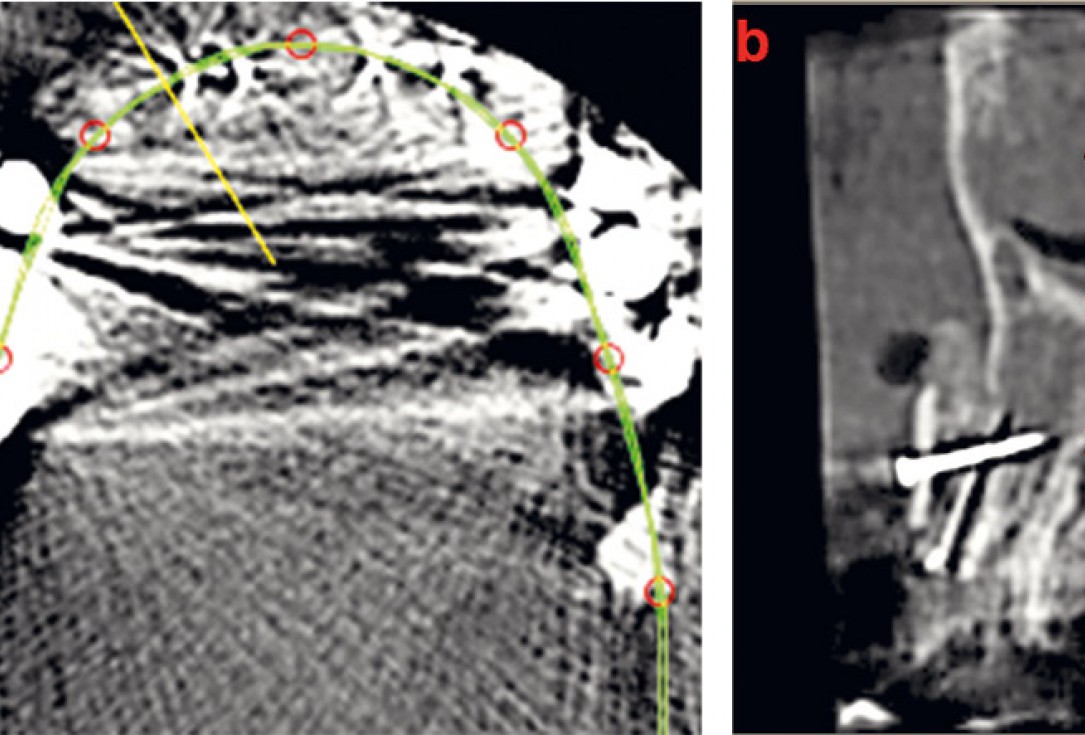

03 / 22 - Initial situation – CBCT image of the first quadrant

04 / 22 - Initial situation – CBCT image of the second quadrant

21 / 22 - CBCT image of the first quadrant one year after augmentation

22 / 22 - Optimal implant position and bone volume stability one year after augmentation